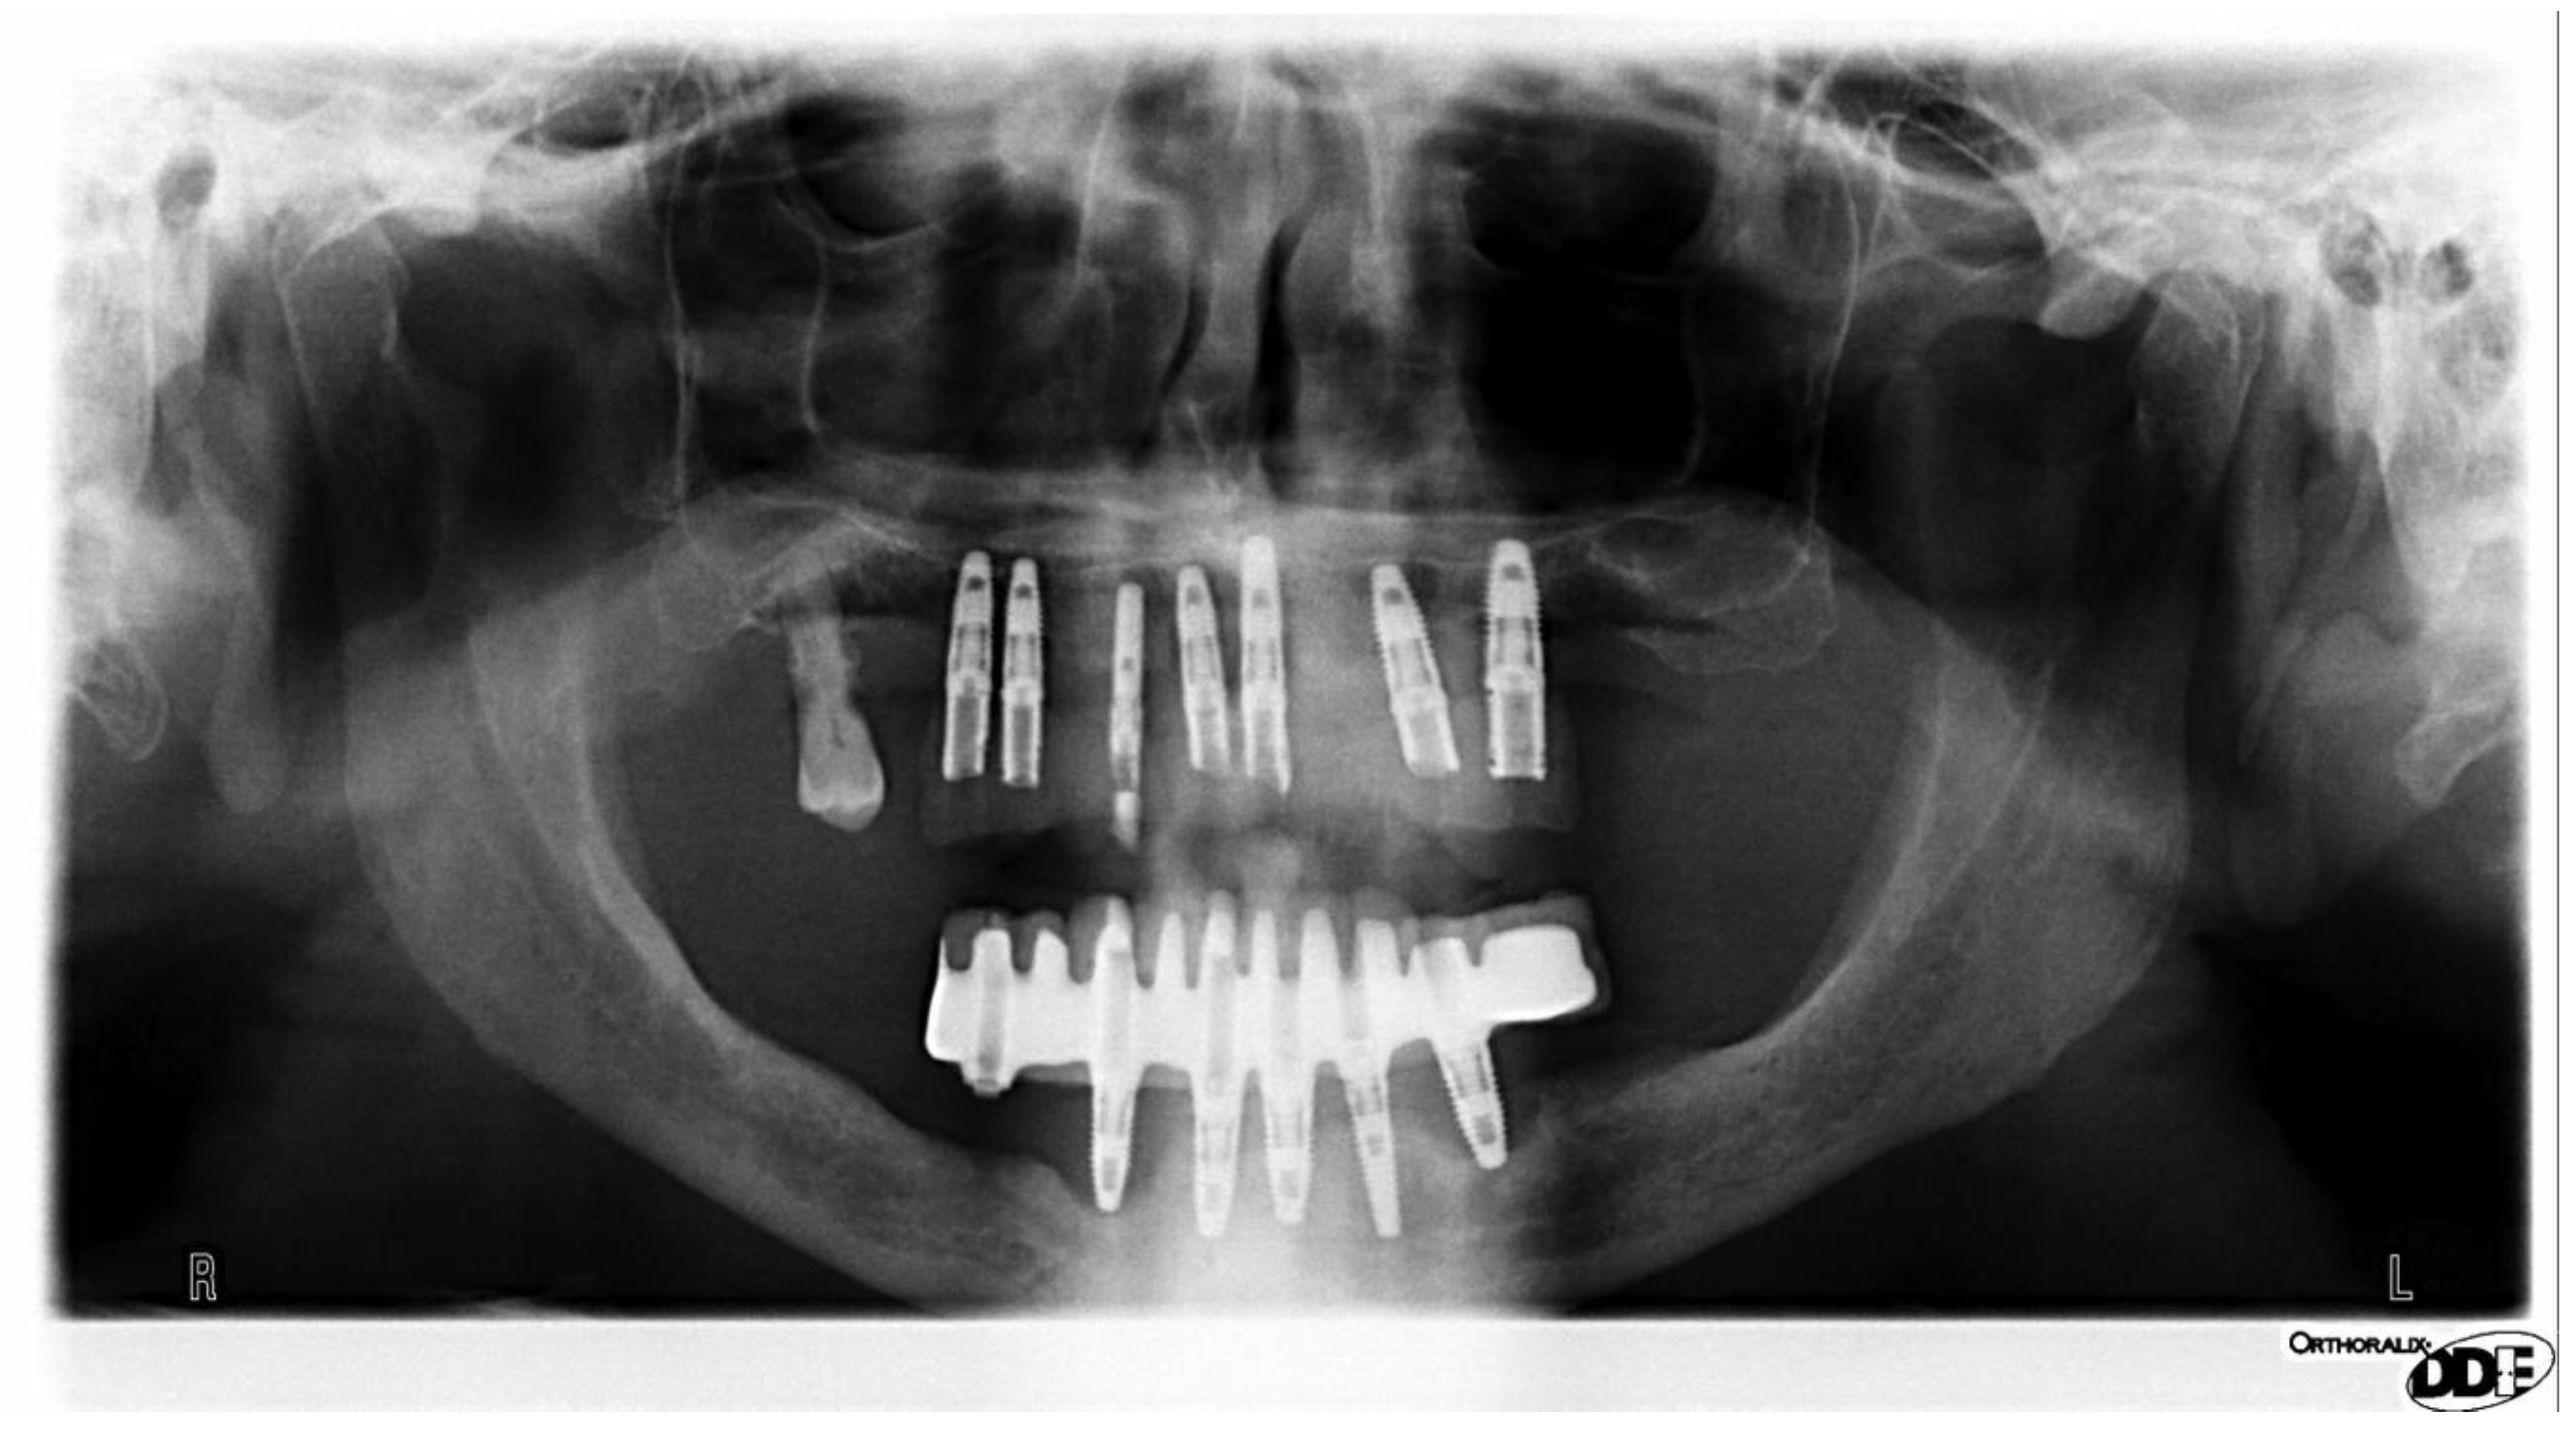

Aspiration of a partial denture after an ischemic stroke Cleveland Negative Aspiration Dental Meaning The negative pressure of aspiration withdraws blood into the cartridge if the needle tip is inside a blood. Intravascular, intraglandular or intramuscular injection; Following a negative aspiration result, the local anesthetic is injected slowly, exerting as little pressure as possible. Foreign body aspiration is a well recognised complication of routine dental care. This is a direct result of the strict. Negative Aspiration Dental Meaning.